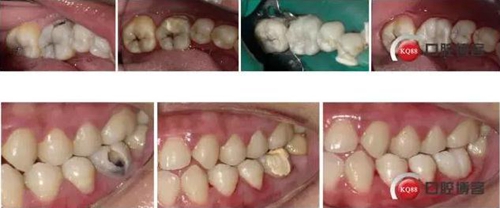

36頰側齲壞發(fā)黑,探診(+),叩診(-),冷刺激(++),松動(-),齦(-)

X-rays示36頰側齲壞達髓角,根尖周無明顯病變

治療:解釋病情,簽訂治療知情同意書,繳費,斯康杜尼+利多卡因局麻下上橡皮障,去腐,開髓,拔髓,10#K銼疏通根管,10#K銼測根長,MB:21mm;ML:21mm;DB:20.5mm;DL:21mm;NSK機擴馬達,21mmPLEX-V銼,扭力:3.5N.cm,轉速:400RPM。P0+EDTA敞開根管口(根管中上1/3),5.25%次氯酸鈉+生理鹽水交替沖洗,干燥,P1+EDTA疏通根管至根管全長,V1、V2+EDTA根管成型,DB,DL根尖1/3融合,5.25%次氯酸鈉沖洗后將次氯酸鈉存于根管內,蕩洗機關水蕩洗20S/根管,蒸餾水蕩洗20S/根管,干燥,隔濕,AHplus糊劑+2506牙膠尖次氯酸鈉消毒后酒精棉球拭干后垂直加壓充填,置小棉球,暫封膏+聚羧酸鋅水門汀暫封。去除橡皮障,拍片。

處理:去除暫封物,上橡皮障,HE面去腐,備洞,富士2墊底,酸蝕,干燥,涂布粘結劑,光照,流體樹脂襯洞,美塑樹脂充填,下橡皮障,調合,打磨,拋光

1、對于頰側齲壞的后牙,有事可以就齲開髓,沒必要直接he面開髓,這樣可以保留更多的牙體組織